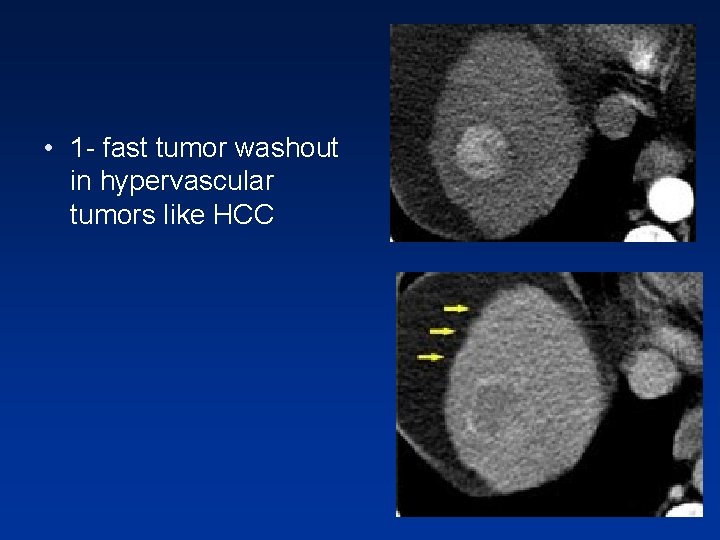

• This phase can be valuable if you are looking for: 1 - fast tumor washout in hypervascular tumors 2 - retention of contrast in blood pool like in hemangioma 3 - retention of contrast in fibrous tissue in capsule ( HCC )or scar tissue ( cholangiocarcinoma or FNH )

• 1 - fast tumor washout in hypervascular tumors like HCC

Relative hypodense lesions in delayed phase • In the delayed phase, malignant tumors ( like HCC ) , the tumor is washed out more than the surrounding liver parenchyma. • But benign tumors typically will not show this kind of wash out , but will stay isodense with liver parenchyma or some times more dense, in the equilibrium phase. • These benign lesions don’t have enough neoplastic neovascularity to have a fast wash out.

• HCC in a cirrhotic liver. Notice fast wash out in equilibrium phase compared to surrounding liver parenchyma.